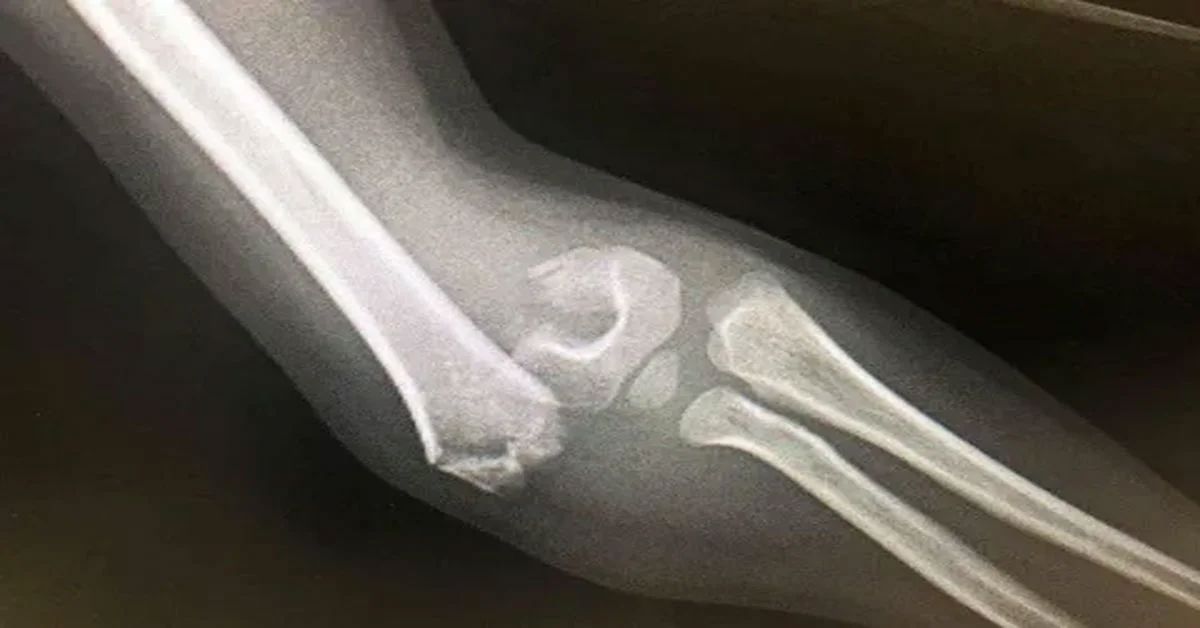

Belirtiler incelendiğinde, Cam kemik hastalığı en sık tekrarlayan kemik kırıkları ile kendini gösterir. Bu kırıklar bazen hafif darbelerle oluşur. Kısa boy, kemik eğrilikleri ve kas zayıflığı da görülebilir. Göz aklarının mavi ya da gri renkte olması ayırt edici bir bulgudur. Bazı bireylerde diş yapısında bozulma ve işitme kaybı da tabloya eşlik edebilir. Belirtiler yaşla birlikte değişkenlik gösterebilir.

Hafif seyreden olgularda kişiler uzun süre tanı almadan yaşayabilir. Kırıklar az sayıda olabilir. Ağır formlarda ise sık kırıklar ve kemik şekil bozuklukları görülür. Bu durum erken tanıyı zorunlu kılar. Düzenli takip süreci önemlidir.